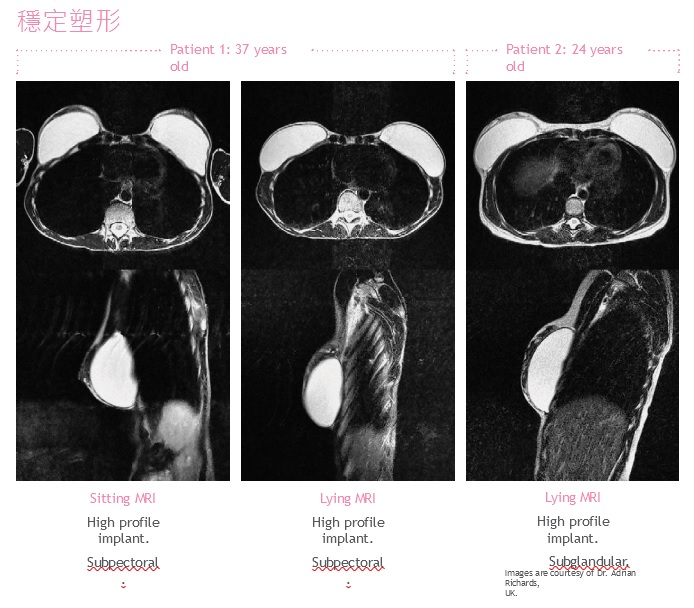

♦凝膠的設計具有塑形穩定性,透過 MRI 顯示,在站立和仰臥位置能顯示自然乳房組織輪廓。